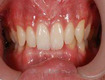

前牙深覆盖对于患者的牙齿美观是有一定的影响的,因此,对于前牙深覆盖的病因查找,是帮助人们早日摆脱该种情况的关键点,下面就为大家分享常见的可引发前牙深覆盖的几种原因。

1 因素一:口呼吸。因鼻呼吸道疾患常造成鼻道部分阻塞,逐渐形成张口呼吸习惯。患者唇肌由于松弛使上前牙唇侧失去正常的压力,两侧颊肌由于拉长而压迫牙弓,使之变窄,形成腭盖高拱,前牙深覆盖合并上颌或牙弓前突畸形。

2 因素二:佝偻病等全身疾病或钙磷代谢障碍。肌肉及韧带张力弱,而引起上颌牙弓缩窄,上牙前突和远中错牙合关系。

3 因素三:不良习惯。长期的吮指、咬下唇及舔上前牙等不良习惯,都给上前牙长期施以唇向推动的压力,从而极易导致上前牙向唇部进行倾斜,而导致下前牙歪向舌部,造成前牙覆盖过大的情况。